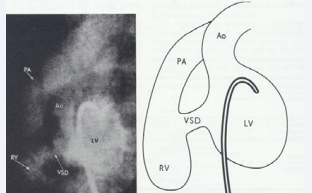

Figure 14 Selected cine frames from left ventricular (LV) angiogram in straight lateral (a) and left anterior oblique (b) views in a patient with Type I tricuspid atresia demonstrating origin of the aorta (Ao) from the LV and the pulmonary artery (P) (white arrow head) from the right ventricle (RV). A large ventricular septal defect (VSD) (black arrow) is also shown [27].

Figure 14: Selected cine frames from left ventricular (LV) angiogram in straight lateral (a) and left anterior oblique (b) views in a patient with Type I tricuspid atresia demonstrating origin of the aorta (Ao) from the LV and the pulmonary artery (P) (white arrow head) from the right ventricle (RV). A large ventricular septal defect (VSD) (black arrow) is also shown [27].

As alluded to in the preceding section, the diagnosis of TA can be made by clinical, chest X-ray, and ECG findings and confirmed by echocardiographic studies, and therefore, cardiac catheterization and selective cineangiography are not necessary to establish the diagnosis [31,37]. There is no need for cardiac catheterization even in those neonates with severe arterial desaturation; the diagnosis of TA made on the basis of clinical and echo-Doppler studies is adequate to make management decisions. However, catheterization may be indicated: 1. If balloon atrial septostomy is necessary and 2. Prior to bidirectional Glenn and Fontan surgery in order to define the pulmonary artery pressures and anatomy. For a detailed discussion of cardiac catheterization and selective cineangiography, the interested reader is referred elsewhere [31,35,37,38]; however, some typical angiographic pictures will be presented in Figures 12 to 17.

Figure 15 Selected cine frames from left ventricular (LV) angiogram in straight lateral view in a patient with Type I tricuspid atresia demonstrating a moderate-sized ventricular septal defect (VSD) in the muscular ventricular septum. Ao, aorta; PA, pulmonary artery; RV, right ventricle [20].

Figure 15: Selected cine frames from left ventricular (LV) angiogram in straight lateral view in a patient with Type I tricuspid atresia demonstrating a moderate-sized ventricular septal defect (VSD) in the muscular ventricular septum. Ao, aorta; PA, pulmonary artery; RV, right ventricle [20].

Figure 16 Selected cine frames from left ventricular (LV) angiogram in straight lateral view in a patient with Type I tricuspid atresia demonstrating origin of the aorta (Ao) from the LV and the pulmonary artery (PA) from the right ventricle (RV). Note a small ventricular septal defect (VSD) in the muscular ventricular septum [1].

Figure 16: Selected cine frames from left ventricular (LV) angiogram in straight lateral view in a patient with Type I tricuspid atresia demonstrating origin of the aorta (Ao) from the LV and the pulmonary artery (PA) from the right ventricle (RV). Note a small ventricular septal defect (VSD) in the muscular ventricular septum [1].

Figure 17 Selected cine frames from left ventricular (LV) angiogram in postero-anterior view in a patient with Type II tricuspid atresia demonstrating origin of the pulmonary artery (MPA) from the LV and the aorta (Ao) from the right ventricle (RV). The RV appears to opacify from the LV via a ventricular septal defect (not labeled) [38].

Figure 17: Selected cine frames from left ventricular (LV) angiogram in postero-anterior view in a patient with Type II tricuspid atresia demonstrating origin of the pulmonary artery (MPA) from the LV and the aorta (Ao) from the right ventricle (RV). The RV appears to opacify from the LV via a ventricular septal defect (not labeled) [38].